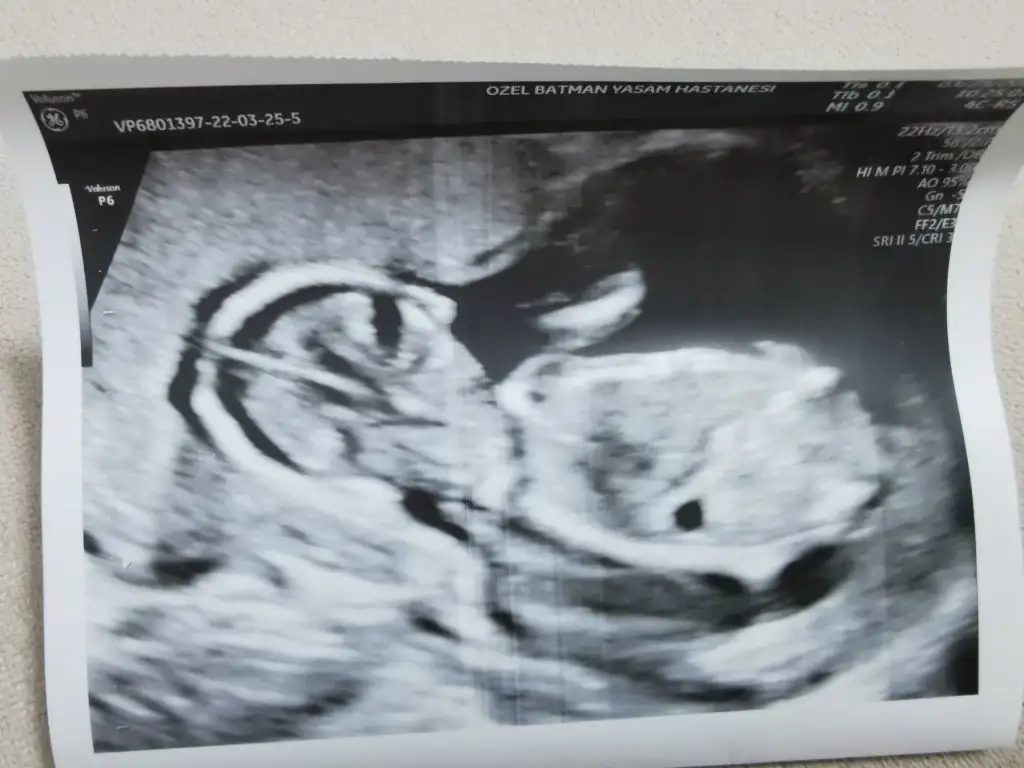

Buda 16+5 ama bacak arasından resim yok maalesef